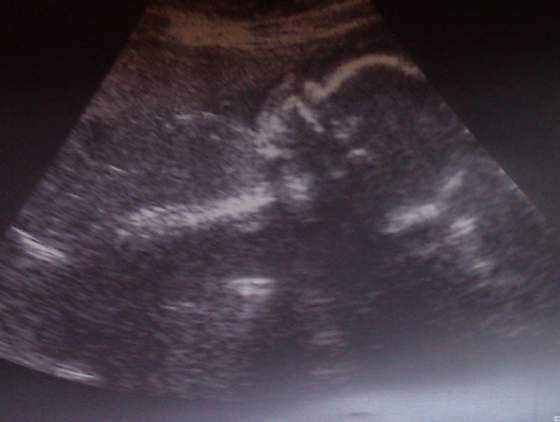

i wszystko ok.Mała grzecznie mamusi posłuchała i sie odwrociła

waga ok 2200 ,według usg wymiary o piec dni wieksze niz z terminu om czyli wszystko w normie

A to buzka mojej Coreczki

zadarty nosek po mamusi